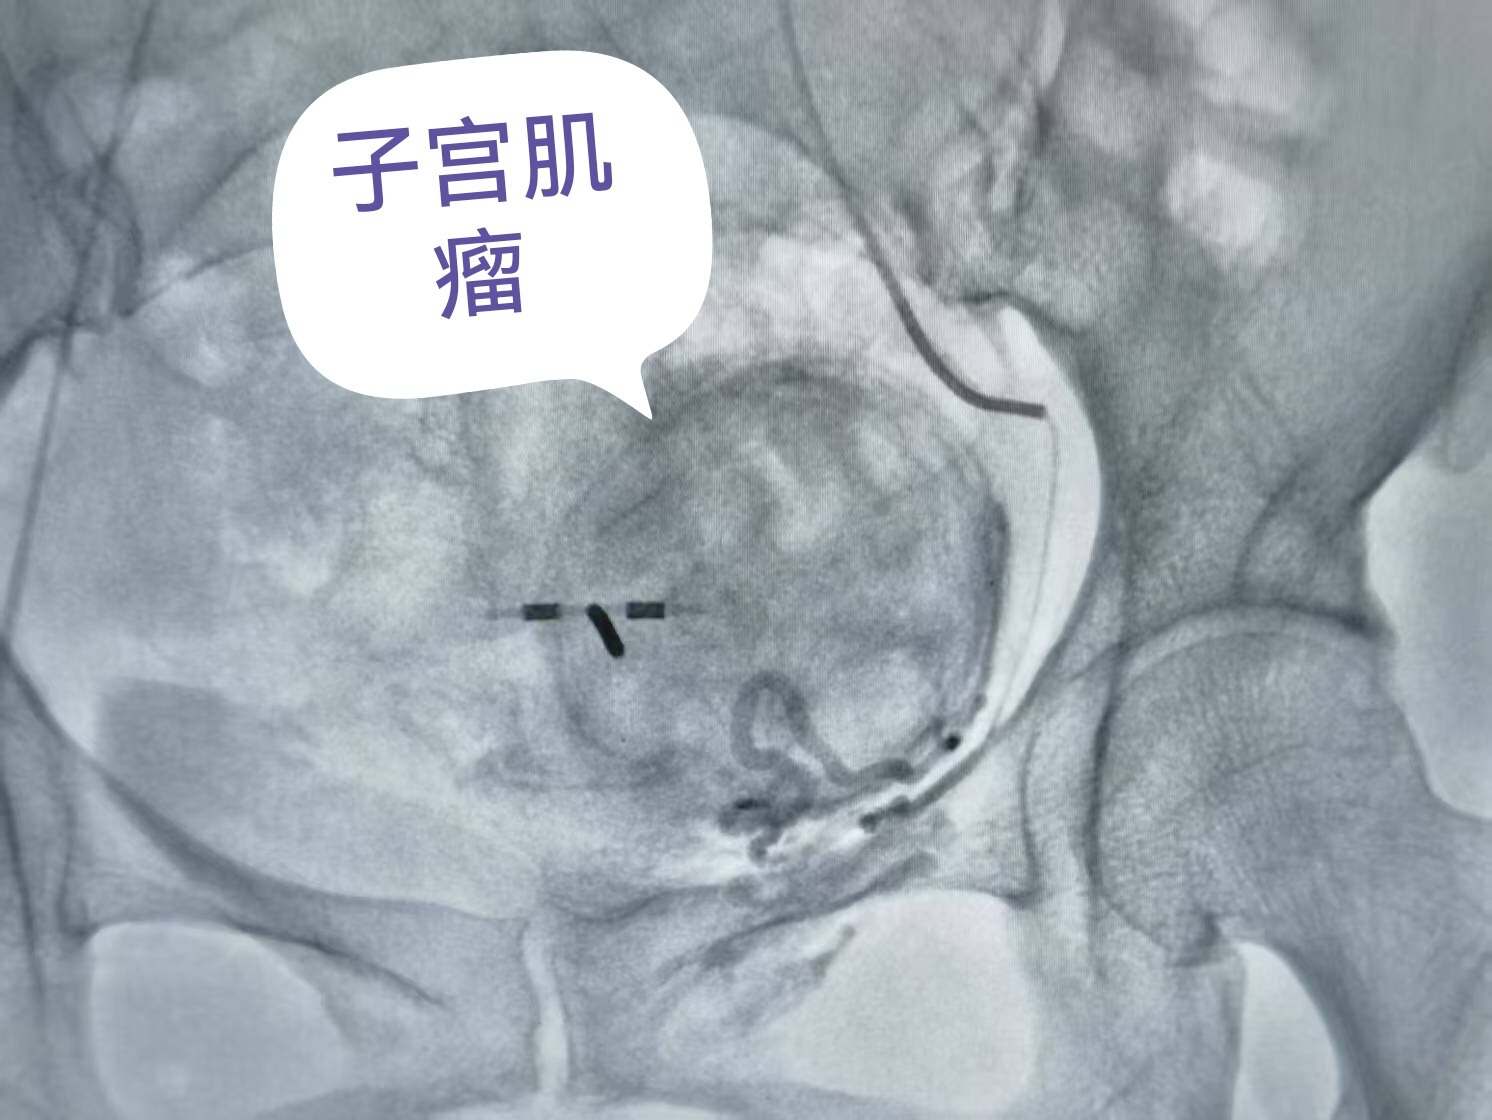

2. 精准栓塞:注入微小的颗粒(栓塞剂),阻断肌瘤的血液供应(图3)。

图3 治疗后造影显示子宫肌瘤的血管被彻底栓塞